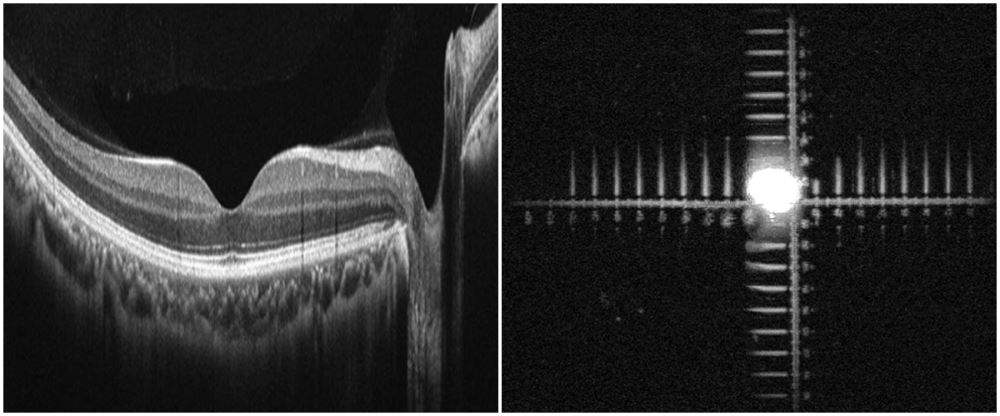

▲ Images of Human Eye’s Retina (Left) and of Standardized Eyeball Phantom (Right) Scanned by OCT Ophthalmic Instruments

The research team led by Dr. Sang Won Lee has developed a standardized eyeball phantom to precisely measure thickness and length. Scanning the standardized eyeball phantom instead of real eyeballs with OCT equipment allows the perfect evaluation of the performance of the equipment.

The standardized eyeball phantom can be comparable to a ruler. The accuracy level of OCT equipment can be measured, and the equipment can be calibrated by comparing the gradations marked on the phantom with the actual 3D imaging measurement of the equipment.

: State-of-the-art medical equipment scanning tomography and cross sections of eyeball tissues, such as the retina. It visualizes the section structure of a certain sample into 3D image and measures the length between different components or layers within tissues by transilluminating lights and then detecting the reflected or single back-scattered lights from the components or layers by using an optical interferometry.